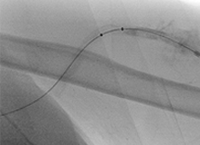

Pharmacomechanical revascularization of extensive iliofemoral thrombus

60 year old female presented with 4 weeks calf pain 1 week swelling.

Procedural steps

• Power Pulse delivery 10mg tPA

• 20 minute dwell time

• ZelanteDVT runtime 415 seconds

• Total case time 90 minutes

Xray of Iliofemoral thrombus pre-treatment and Power Pulse™ delivery

Iliofemoral thrombus pre-treatment (left) and Power Pulse delivery (right)